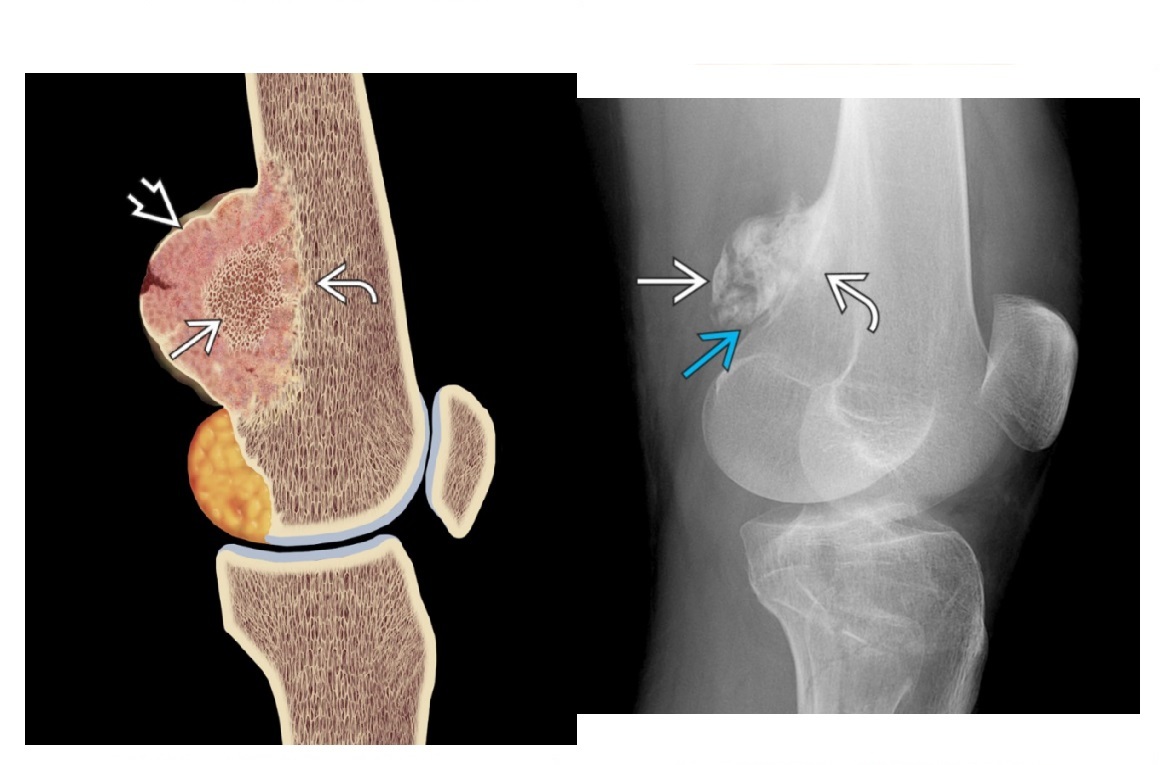

Segond fracture

Lateral tibial plateau

Associated with ACL tear (75%) and internal rotation

MR SL = Medial Reverse Lateral Segond

How well did you know this?